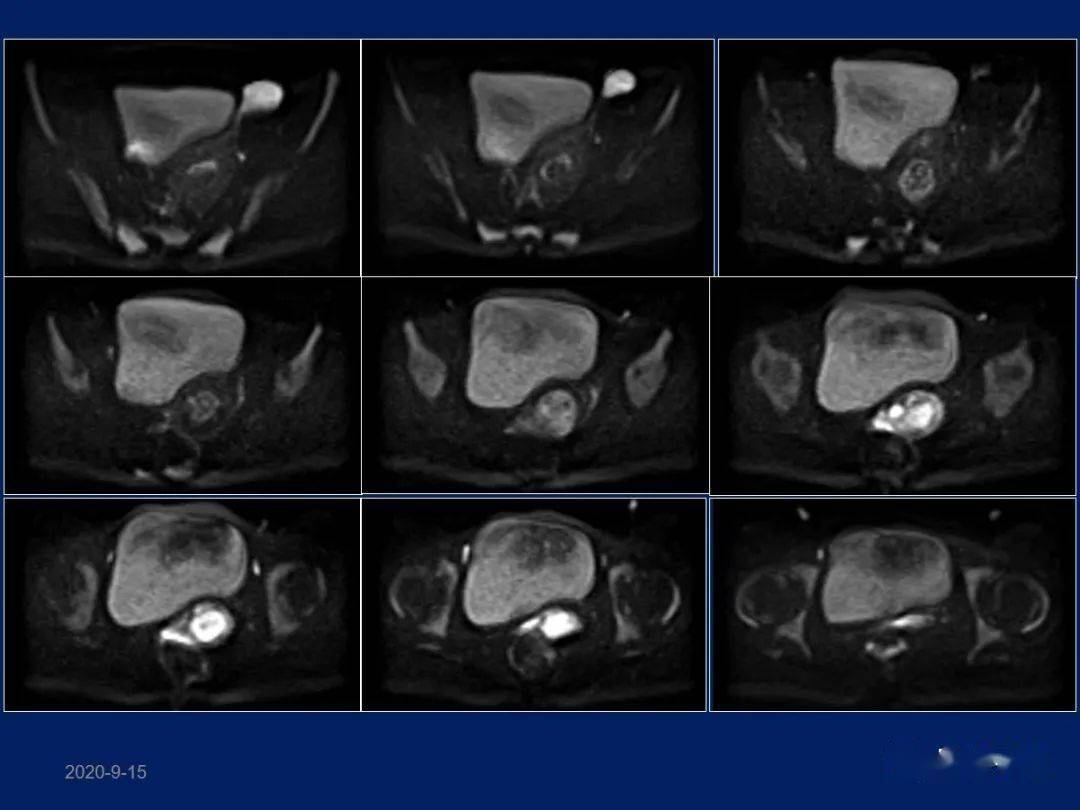

子宫憩室核磁共振图片

子宫憩室核磁共振图片,子宫憩室图片

直到做超声和核磁共振检查,才发现了问题 剖宫产切口憩室.

涨知识核磁共振下的子宫

宫腹联合治疗子宫憩室1例

妇产科常见疾病mri表现_子宫